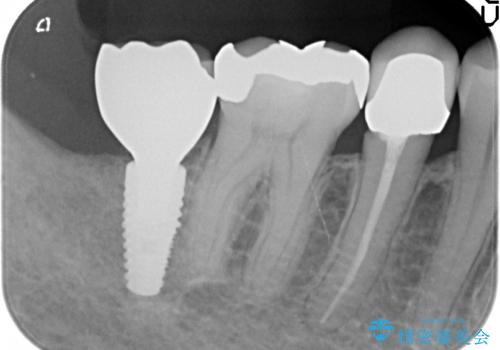

- 右下7番にインプラント治療を行った症例です。

CT撮影を行い状態を確認後、インプラント(ストローマン)の埋入(一次手術)を行いました。

インプラントと骨の定着を待った後に二次手術を行い、カスタムアバットメント、オールセラミッククラウンによる補綴を行いました。